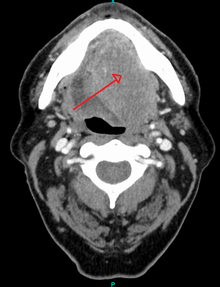

Head and neck cancer

Ninety percent[14] of cases of head and neck cancer (cancer of the mouth, nasal cavity, nasopharynx, throat and associated structures) are due to squamous cell carcinoma.

Squamous cell carcinomas of the head and neck have been found to have a greater risk of metastasis to the local nervous system, lymphatic system, hence possibly reducing treatment efficacy.[34]